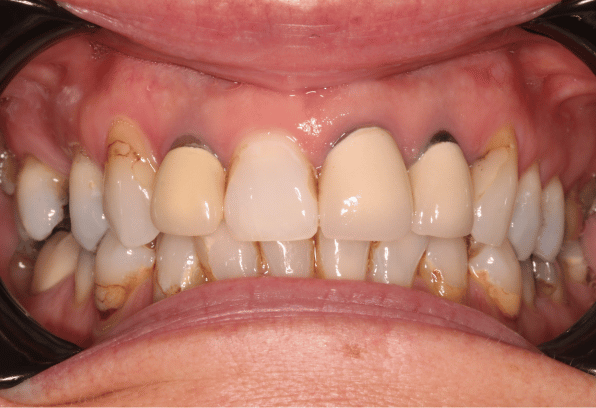

After

After

Read MoreA smile makeover with an implant on the front incisor, bone graft and soft tissue graft. The smile was enhanced with composite bonding to give…